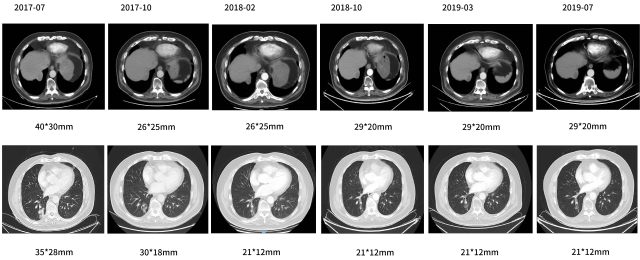

2017-07-25—

二线:CM082+依维莫司

影像学评估—最佳评效 PR

影像学评估

伏罗尼布联合依维莫司患者获得长生存病例。